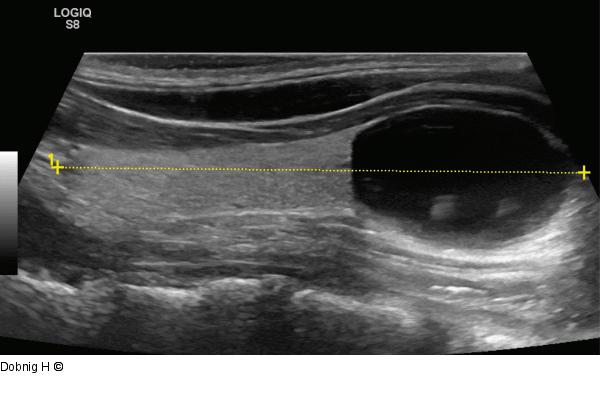

Abbildung 5: Alkoholablation - Schilddrüse Patient mit einer einkammrigen Schilddrüsenzyste, im Ultraschall dünnwandiger, unauffälliger Zystenbalg (Sagittalebene). |

Patient mit einer einkammrigen Schilddrüsenzyste, im Ultraschall dünnwandiger, unauffälliger Zystenbalg (Sagittalebene). |